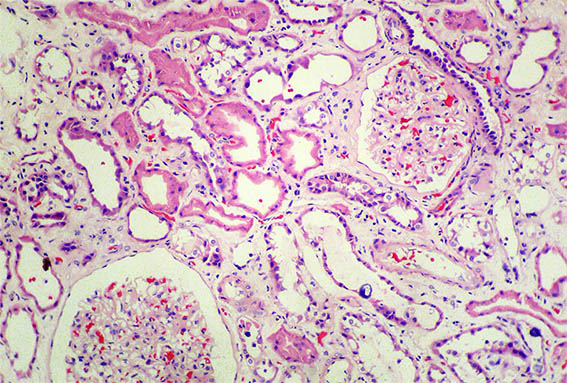

Kidney biopsy is done. Look at the pictures.

Figure 1. H&E, X100. Note the prominent tubulointerstitial involvement.